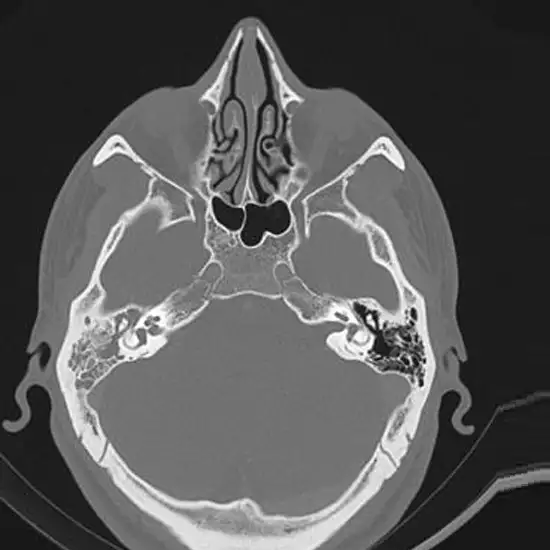

A CECT Both Mastoid is a Contrast-Enhanced Computed Tomography scan of both mastoids. It is an imaging scan that uses an x-rays beam and contrast material to obtain detailed images of the mastoids (The part of your skull behind the ear). The scan helps evaluate the delicate structures of the ear and surrounding tissues.